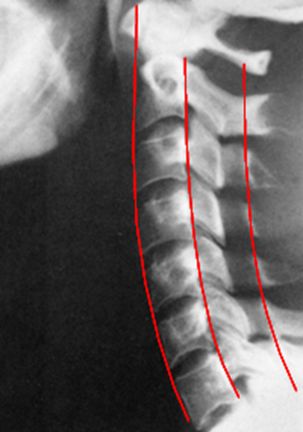

图6-2 颈椎侧位DR平片

1 枕骨 occipital bone 2 第2颈椎棘突 2nd cervical spinous process

3 关节突关节 zygapophyseal joint

4 下关节突 inferior articular process

5 上关节突 superior articular process

6 第4/5颈椎间隙 4th/5th cervical intervertebral space

7 横突 transverse process 8 第3颈椎 3rd cervical vertebra

9 颈2/3椎间孔 2nd/3rd cervical foramen intervertebrale

10 齿状突 odontoid 11 寰椎前弓 anterior tubercle of atlas

![]()